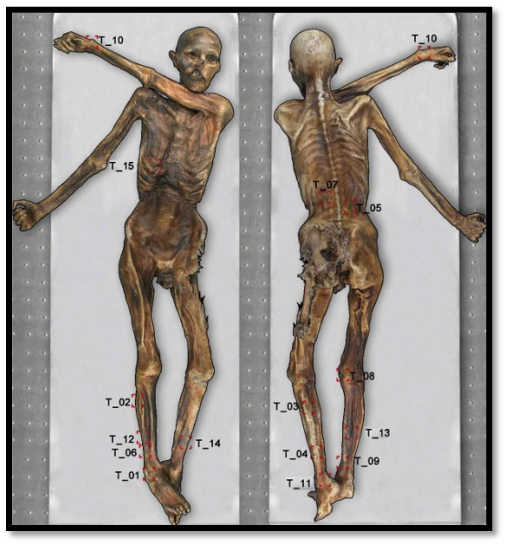

Τα Τατουάζ

Ο Ötzi έφερε 61 τατουάζ. Σε αντίθεση με τα σύγχρονα τατουάζ, δεν έγιναν με βελόνα. Πρόκειται για λεπτές τομές στο δέρμα, μέσα στις οποίες είχε τριφτεί κονιοποιημένος άνθρακας.

Από τα σημεία του σώματος που επιλέχθηκαν για τα τατουάζ αυτά (σημεία τα οποία καλύπτονταν τις περισσότερες φορές από τον ρουχισμό) οι επιστήμονες υποψιάζονται ότι επρόκειτο για μια πρώιμη μορφή θεραπευτικής πρακτικής, παρόμοια με τον βελονισμό, με στόχο την εξάλειψη του πόνου.